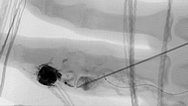

Fluoroscopic view of the cast after successful nidus embolization of the AVM. To improve the overview for surgical planning, this image is also shown without subtraction with visible bone.